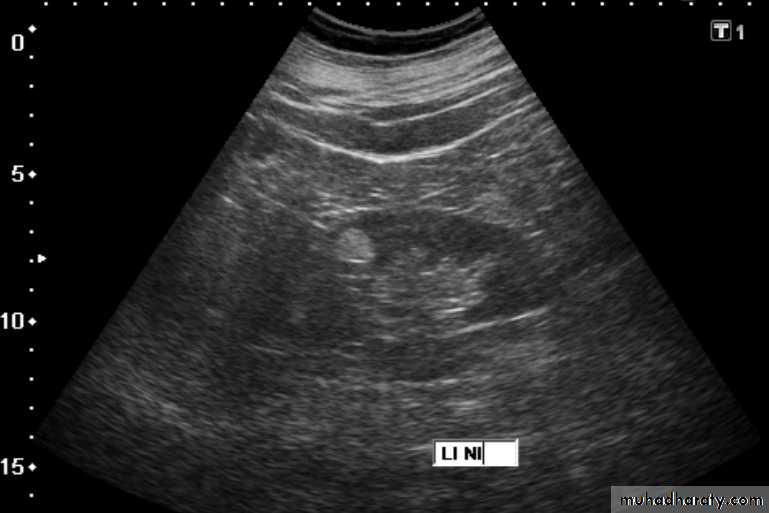

Renal ultrasound

• US is the 1st line investigation.Normal renal ultrasound shows:

• Smooth renal outlines• Renal parenchyma is of homogenous echoes that is similar or less reflective than the adjacent liver or spleen.

• Renal parenchymal surround the central echo complex.

• PCS and ureters are normally not visible